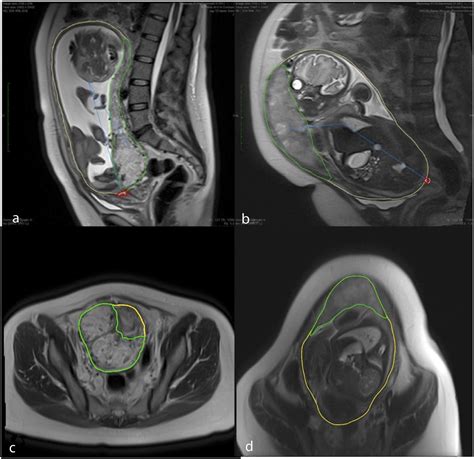

• Suspected Fetal Anomalies: MRI can provide detailed images of the fetus, helping to detect and diagnose congenital anomalies that may not be visible on ultrasound.

• Placental Abnormalities: MRI can help identify placental abnormalities, such as placenta previa or placental abruption, which can pose risks to both the mother and the fetus.

• Maternal Conditions: MRI can be used to diagnose and monitor maternal conditions that may affect pregnancy, such as pelvic pain, back pain, or neurological symptoms.